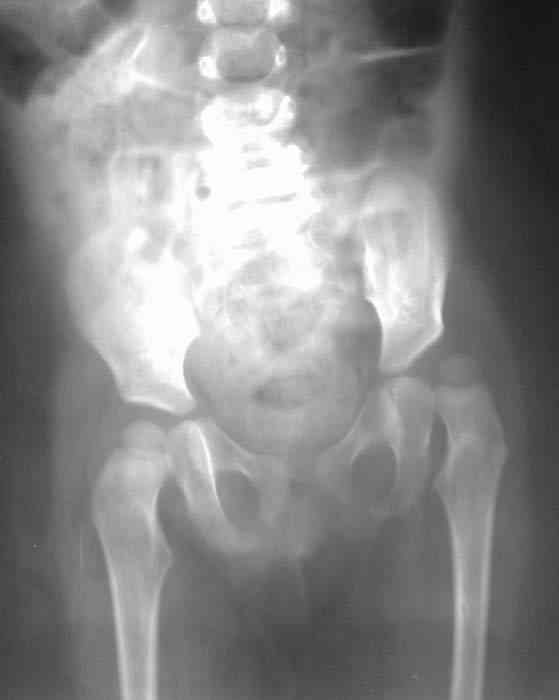

Уважаемые коллеги!Окажите, пожалуйста, консультативную помощь! Девочка, 1 г 9 мДЗ: врожденная патология головного мозга, врожденная дисплазия, подвывих, приводящая контрактура левого тазобедренного сустава, микроцефалия, миоклонические припадки, грубая задержка психофизического развития, с-м Айкарди?

Особенности объективного осмотра в настоящее время:Умеренный тетрапарез. Признаки рахита (деформация костей черепа, четки). Дыхание пуэрильное. Тоны сердца ритмичные, шумов нет. Живот мягкий, безболезненный, печень +1,5 см. Склонность к запорам. Местный статус: резкое приведение левого бедра, относительное укорочение левой нижней конечности. Ограничение отведения в тазобедренных суставах, особенно слева. Гипертонус мышц левой нижней конечности. Ограничение сгибания в левом коленном суставе.

Объем движений (левый ТБС): сгибание-разгибание (фиксированное) 65-165; разведение - D 45, S 65. Положение сустава по отношению к линии Розера-Нелатона - D 0,5 см, S 1,5 см. Хронаксиметрия - возбудимость нервных стволов нижних конечностей в норме, двигательная реакция мышц типичная.

Hi, this is pretty typical windblown hip deformity: abduction on rt side, adduction on the lt(according to your anamnesis kind of CP. Lt side already subluxated , no treatment will lead to further dislocation.I think that best way for treatmen now is : adductor tenotomy on the lt + spica cast ( 50-60 degrees abduction with wood bar between legs), after 6 weeks change to another 6 weeks; than for 6 months night plastic abduction brace.